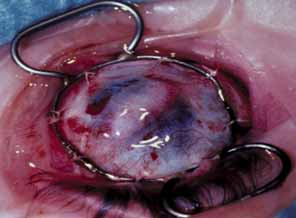

Waring, 19771653 y2 y–5 y11 (1/9)

Beauchamp, 19791744 y3 mo–26 y50 (9/18)

Schanzlin, 19801754 y1 y–10.2 y60 (9/15)

Stulting, 198416630 mo2 mo–6 y68 (31/45)